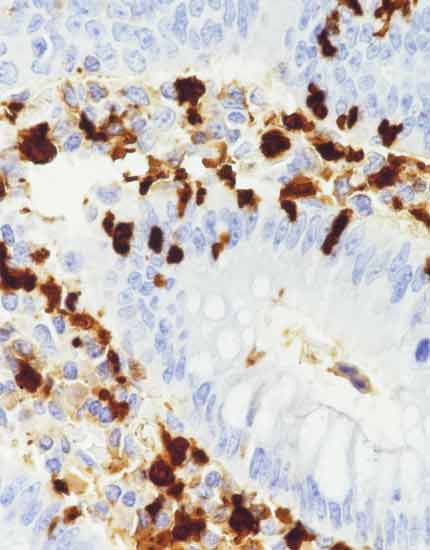

产品名称:CEA

产品编号:MAB-0852

阳性部位:胞质

图片描述:

结肠腺癌,CEA染色,胞质阳性